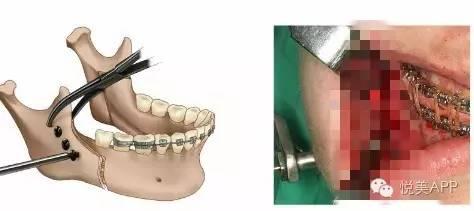

第二步:正颌外科手术,将长出来的部分骨头切除,然后往回推,固定住,形成正确咬合状态~

第一种:下颌骨矫正——将下颌骨截骨,去除一段,整体后退,固定,不但缩短下颌的长度,而且在后退的同时伴有上颌骨向上旋转,下颌角的角度变小,侧面也更好看,如果下巴颏太长,还可以缩短。

移动远心骨段之后~固定

固定

检查咬合并固定

第三步:恢复后进行,术后正畸,精细化调整咬合。